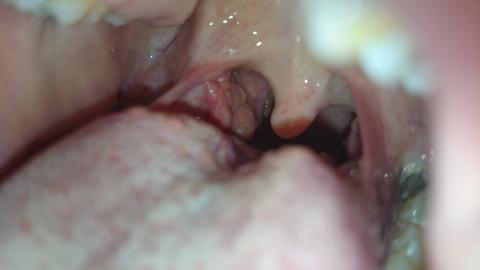

Lucie88 - 2.3.2016 22:35:05 Dobry den, prosim o radu, uz asi tri tydny mam pocit neceho v krku, nejde to spolknout a prekazi to pri jidle. Pri pohledu do krku jsem zjistila ze mam u mandle nejaky vyrustek. Mam to jen na jedne strane. Co by to prosim mohlo byt? Mam hrozny strach z nadoru .. Dekuji za odpoved.

Dobrý den, fotografie není příliš přehledná, ale v oblasti před pravou mandlí se mi zdá drobný váček - cystička. Nejde o nic vážného, většinou je to důsledek nějakého mechanického podráždění, časem to zmizí. Zkuste kloktatdla, např.heřmánkového čaje.